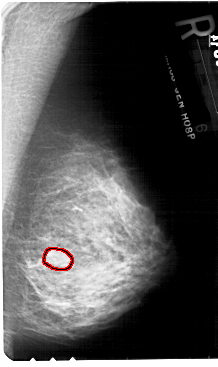

A_1781_1.RIGHT_MLO

RIGHT_MLO LINES 5491 PIXELS_PER_LINE 3256 BITS_PER_PIXEL 12 RESOLUTION 43.5 OVERLAY

FILE: A_1781_1.RIGHT_MLO.OVERLAY

TOTAL_ABNORMALITIES 1

ABNORMALITY 1

LESION_TYPE MASS SHAPE OVAL MARGINS ILL_DEFINED

ASSESSMENT 4

SUBTLETY 3

PATHOLOGY BENIGN

TOTAL_OUTLINES 1

BOUNDARY